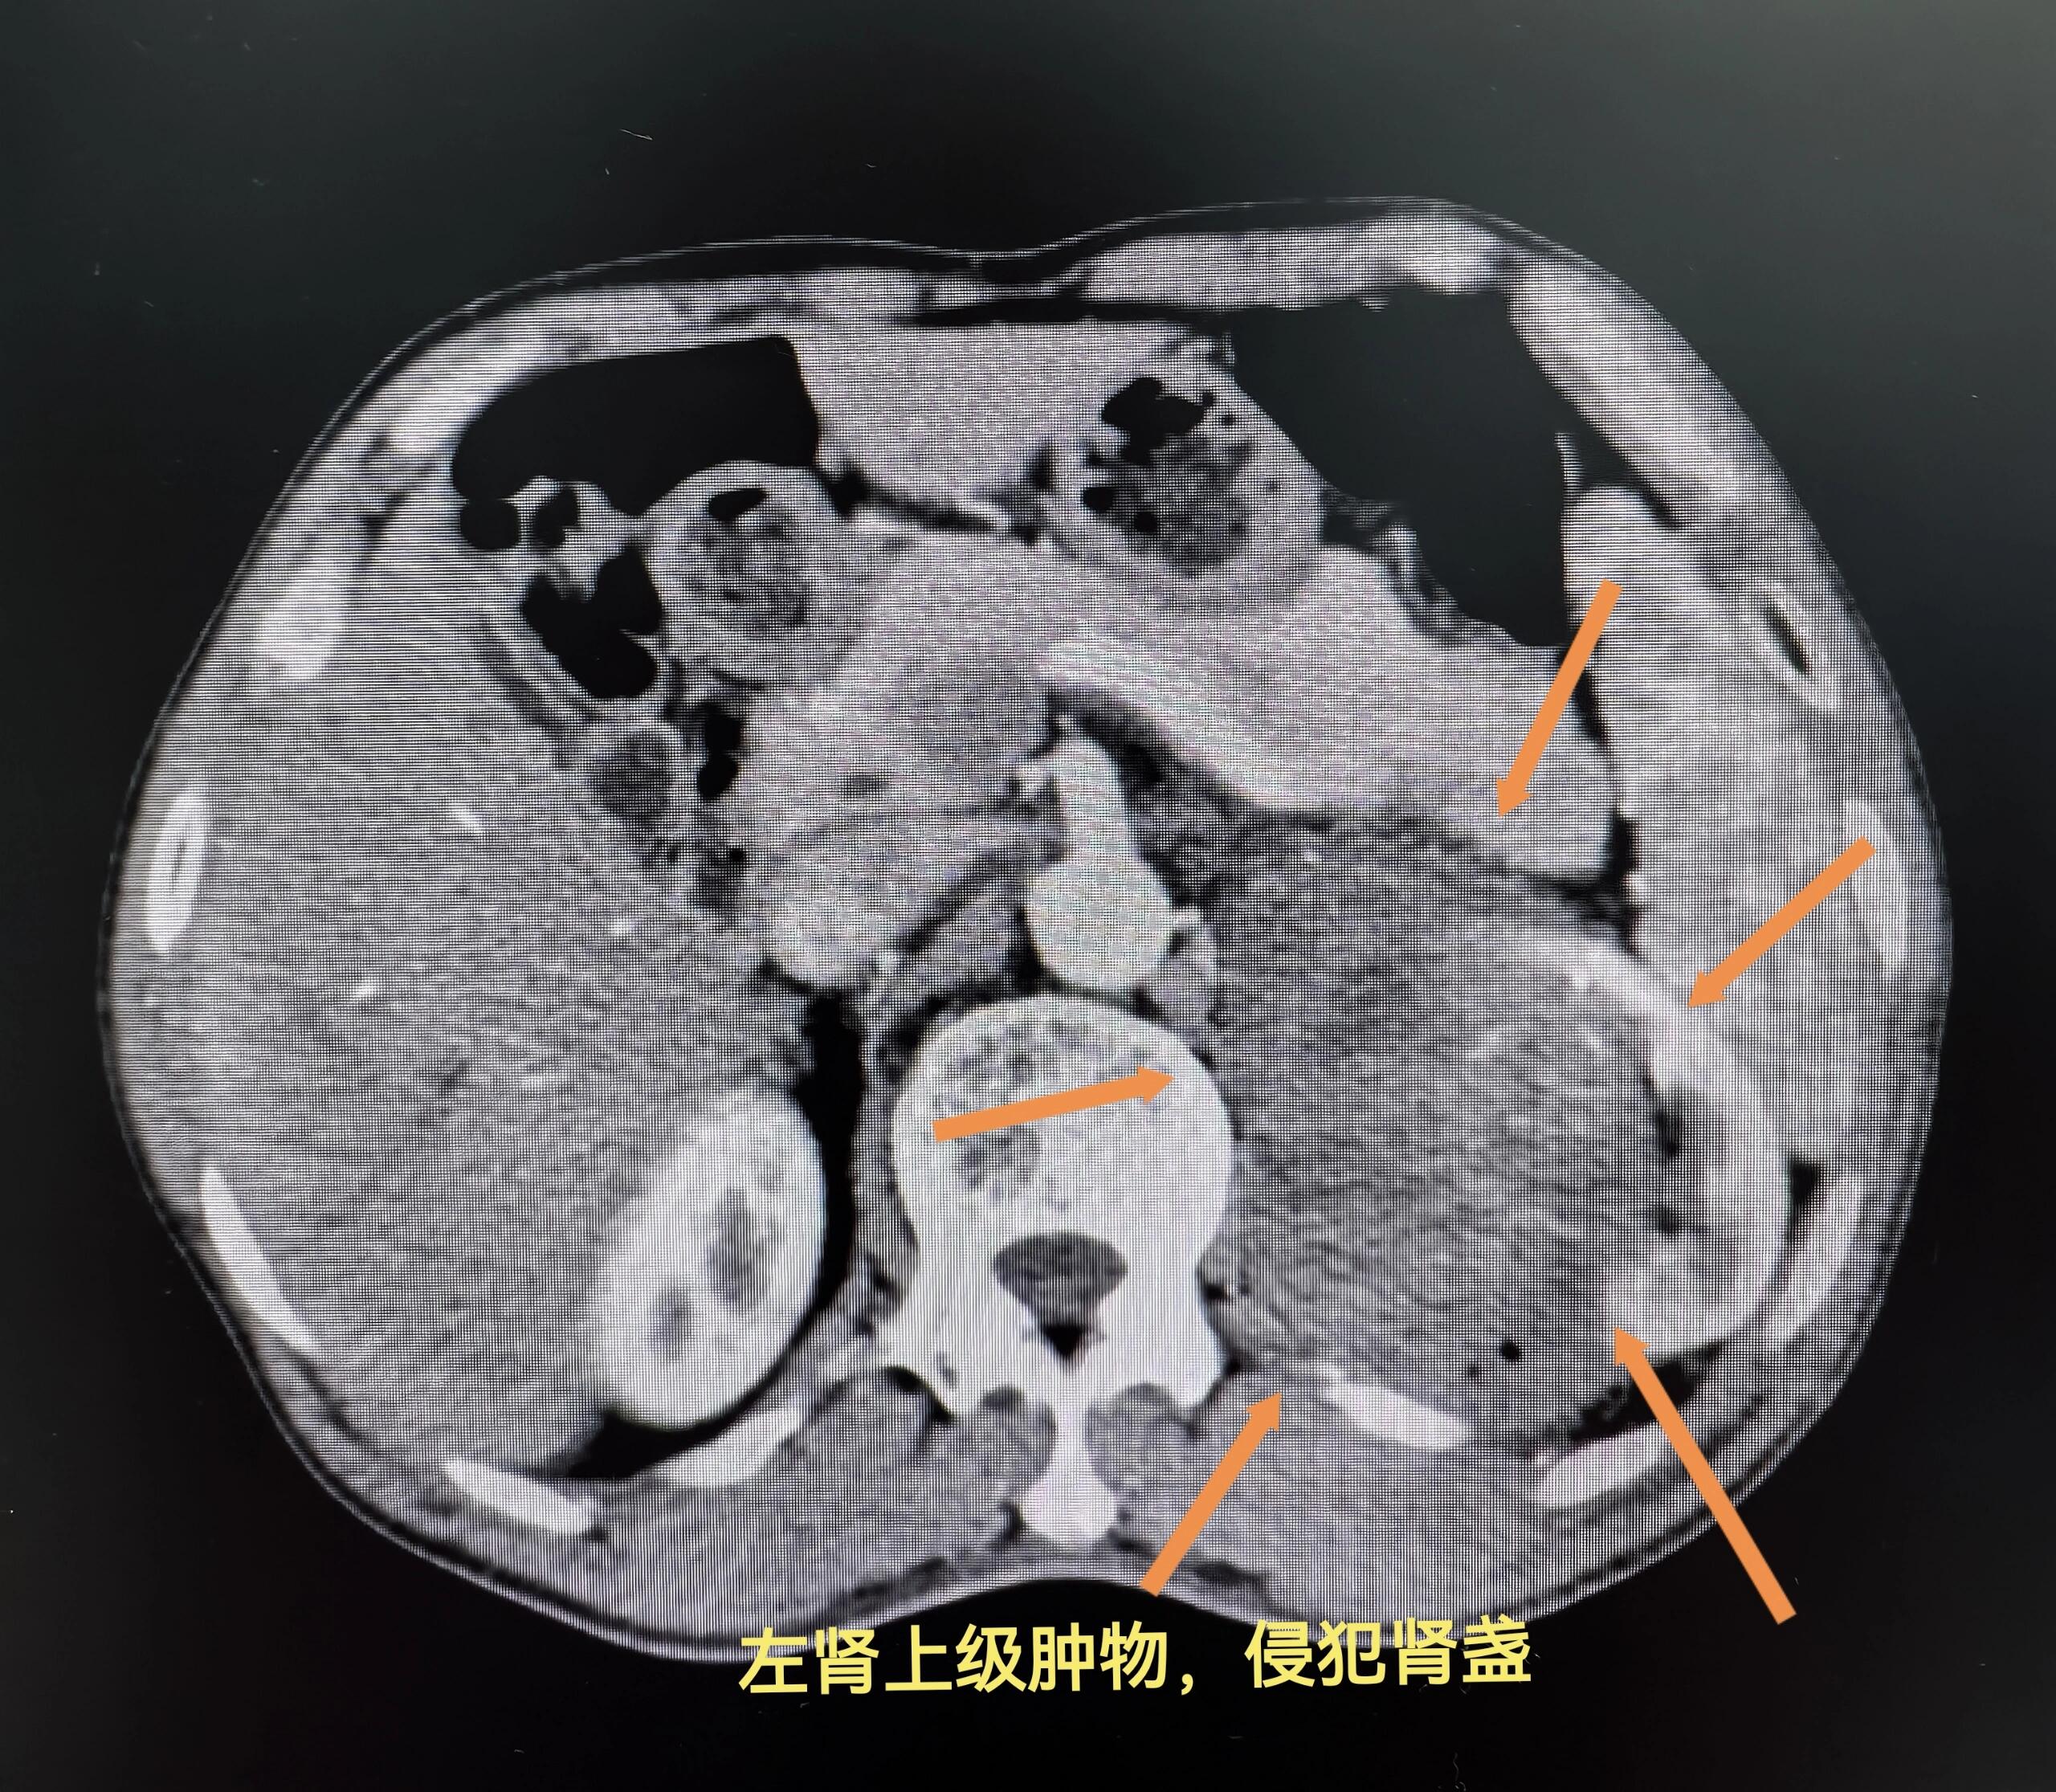

呼吸困难加重肾癌晚期如果出现肺转移,可能会导致呼吸困难症状明显加重氧饱和度下降患者体内氧气含量可能明显降低咯血咳嗽咳痰加重这些症状也可能伴随呼吸功能衰竭而出现盆腔转移相关症状盆腔巨大包块肾癌晚期可能出现盆腔转移,形成巨大包块肠道压迫或肠瘘包块可能压迫肠道,甚至导致肠瘘;骨痛和骨折则可能是因为肿瘤转移到骨骼,导致骨质破坏或骨质疏松,从而引发疼痛和骨折咳嗽和咯血可能提示肿瘤侵犯了肺部或肺转移的存在值得注意的是,肾癌的症状可能因人而异,且早期肾癌可能没有任何明显症状因此,定期进行体检和早筛对于早期发现和治疗肾癌至关重要一旦出现上述症状,尤其是持续的;晚期如果肾癌不和集合系统交通,只是可以在体表发现包块,病人感觉乏力虚弱或者体重降低如果肾癌位于肾盂,除了发现包块以外,可以出现尿中带血,这种血是全程的无痛性血尿,而且尿中的红细胞是均一性的红细胞,病人可以出现恶病质,也就是患者出现乏力厌食体重减低贫血等恶病质的表现;肾癌晚期的症状主要包括以下几点1 三联征症状 血尿由于肾癌晚期侵犯肾脏的集合系统,引起出血,患者常出现血尿 肿块随着肿瘤体积的增大,患者腰腹部可触及肿块 腰腹部疼痛肿瘤长大后,局部会出现疼痛2 肾外非典型症状 贫血部分患者可能表现为贫血症状 红细胞增多少数患者可能出现红。